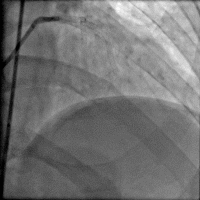

冠脉造影

造影时间: 入院当天03:35~03:52。

造影结果(一): 前降支近段闭塞,回旋支中远段90%狭窄。

造影结果(二): 右冠中段闭塞。

造影结论及应对策略: 前降支近段闭塞,回旋支中远段90%狭窄,右冠中段闭塞,未行左室造影。病变血管:前降支;回旋支;右冠。与家属沟通,同意行PCI。